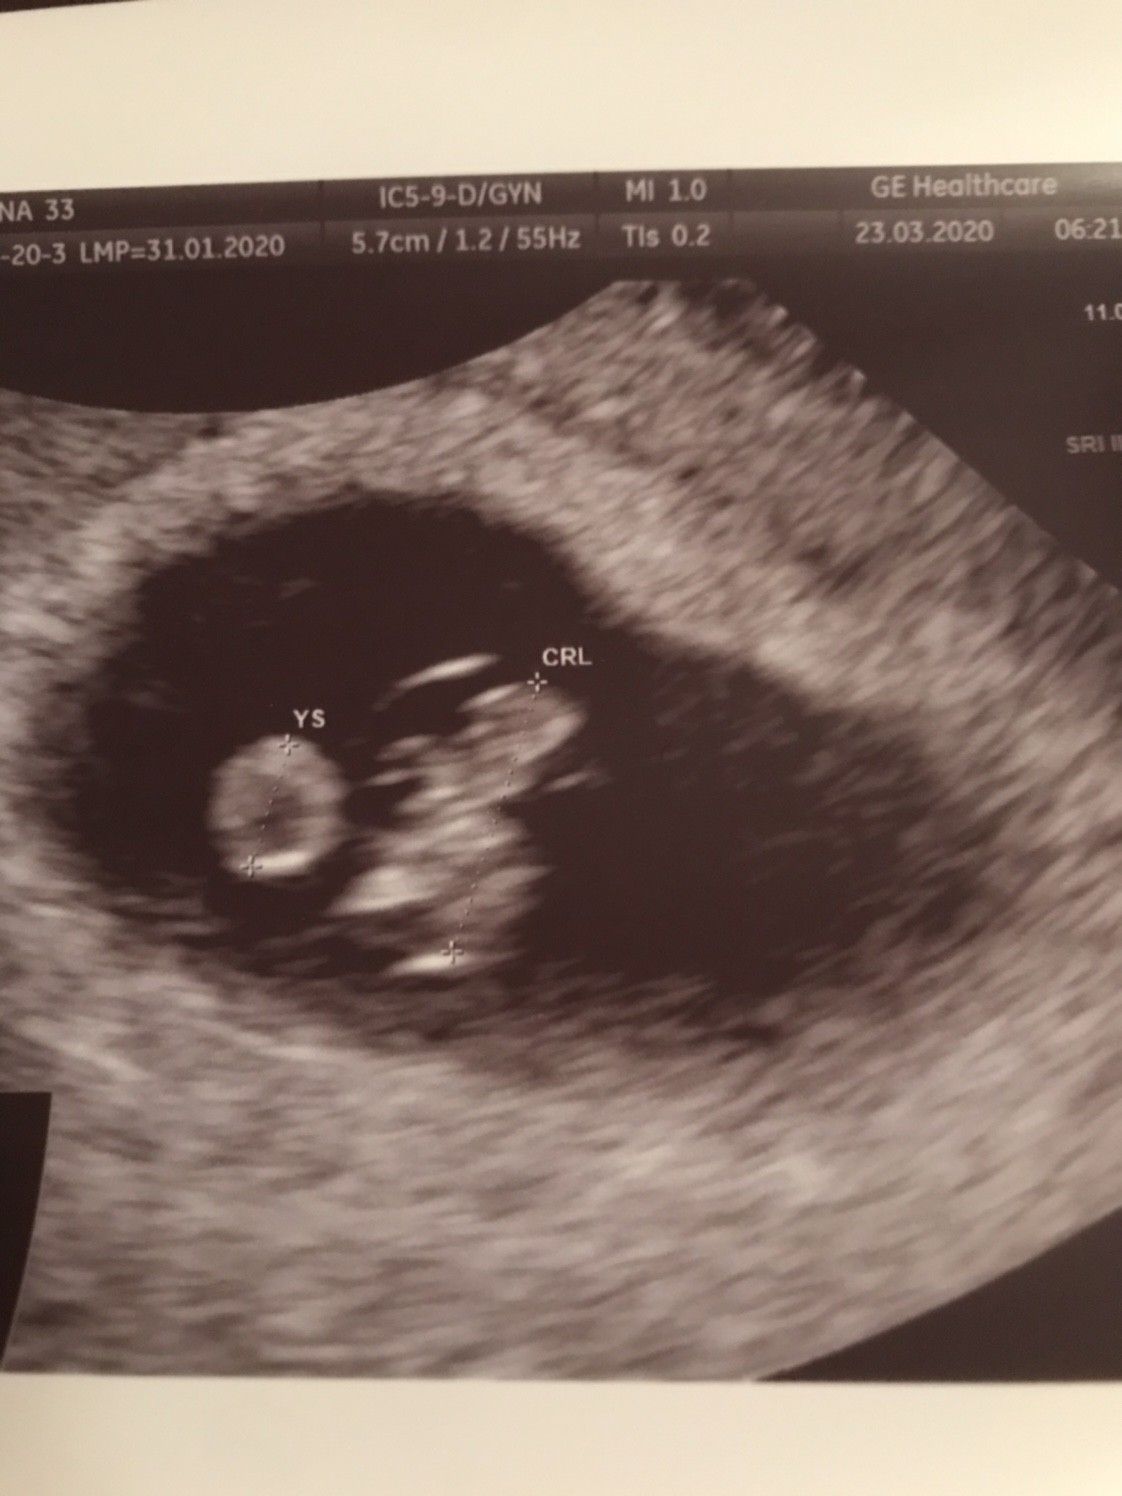

Dziewczyny jestem już po wg usg 7+2, serce jak dzwon wszystko w porządku

Zobacz załącznik 1095794